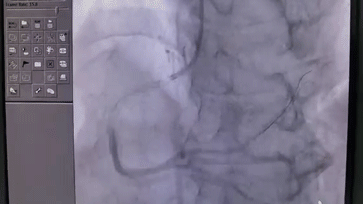

开始造影,发现右冠状动脉完全闭塞。

阻塞血管恢复通畅,导丝顺利通过闭塞段,阻塞血管重现了血流。

至此,我院胸痛中心团队创造了 D-to-W 时间仅 23 分钟的纪录。